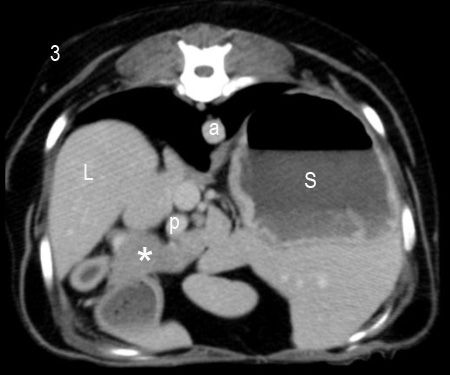

Because of the highly vascular nature of insulinomas, these tumors typically show intense enhancement (hyperattenuation) in the arterial phase, compared with normal pancreatic parenchyma, with similar enhancement to normal pancreatic tissue in the venous phase.7,8 A more recent paper suggested that the pattern of enhancement may be more variable, with hypoattenuating lesions seen as commonly as hyperattenuating lesions in at least one phase.9 While further studies including larger numbers of cases are needed to better define the CT imaging characteristics of insulinomas, CTA remains the best imaging modality for the identification and staging of these tumors (Figure 2).

Figure 2. Transverse CT images of the dog in this case at the level of the pancreatic body and left limb, obtained pre-contrast (1), and in the arterial (2) and portal (3) phases of enhancement (1 ml/lb of iodinated nonionic contrast medium, 300 mg iodine/ml). A small, 1-cm nodule is visible ventral to the portal vein in the arterial phase of enhancement (arrows), but not pre-contrast or in the portal phase. This nodule was surgically resected and confirmed to be an insulinoma on histopathologic examination. L: liver; S: stomach; a: aorta; p: portal vein; C: caudal vena cava; asterisk (*): pancreas.References